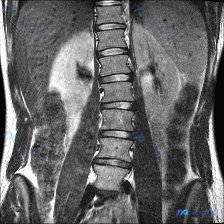

用户是因为怀疑脊柱侧弯去做的检查,拿到的是腰椎MRI(T1加权像,冠状位)。

- 腰椎序列在冠状面上排列基本规整,各椎体高度、信号均匀

- 未见明显的侧弯弧度、椎体破坏或巨大软组织肿块

- 椎间隙、椎间孔、小关节、旁脊肌肉也都没看到显著异常

但问题也来了——这份MRI是仰卧位、只扫了局部腰椎,也没有T2/STIR这些序列。